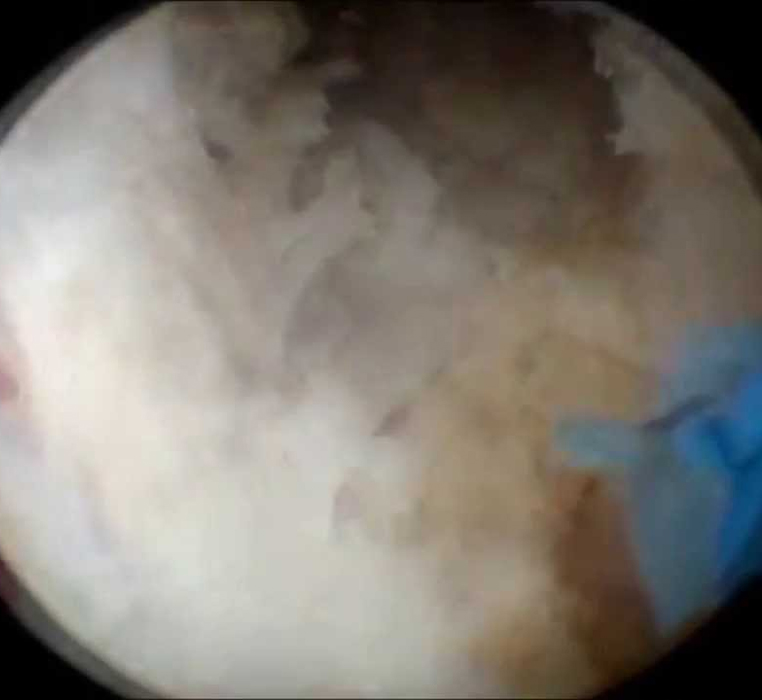

Uretrocistofibroscopía Rígida

Uretrocistofibroscopía flexible